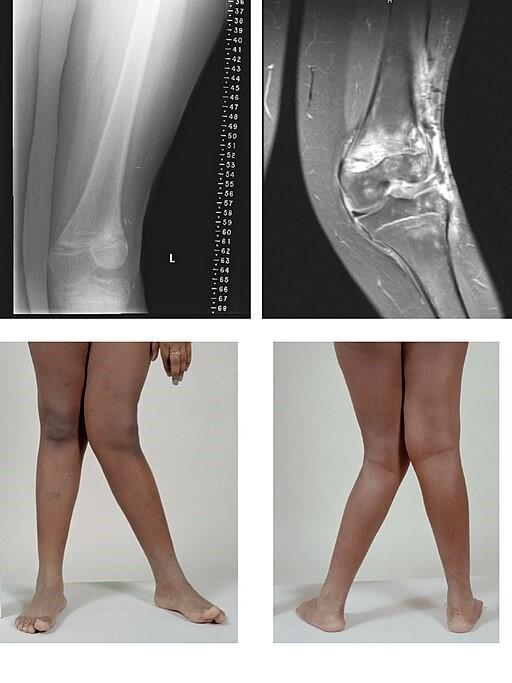

Valgus

Von BioMed Central, CC BY 2.0, über Wikimedia Commons